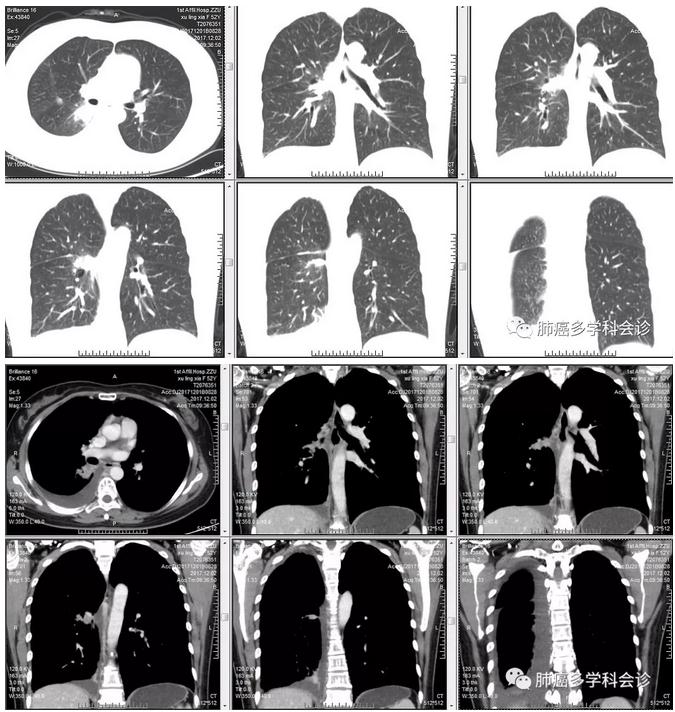

2015年3月因咳嗽、痰中带血、左侧肋骨下缘疼痛就医,CT发现右肺门一个3.4×3.0cm软组织肿块,呈浅分叶状,边缘毛糙,右肺多发结节影,右侧胸膜局部结节样突起,胸椎部分椎体内小片状骨质缺损影,纵膈淋巴结肿大。PET-CT:肺占位并颈椎转移。

2017.10.13复查CT:肺部疾病进展,右肺多发小结节。患者开始重新改用“特罗凯”直今,未做疗效评价。也没有明显的症状。

以下是患者在2017年12月的胸部CT、气管镜活检病理和基因检测结果: